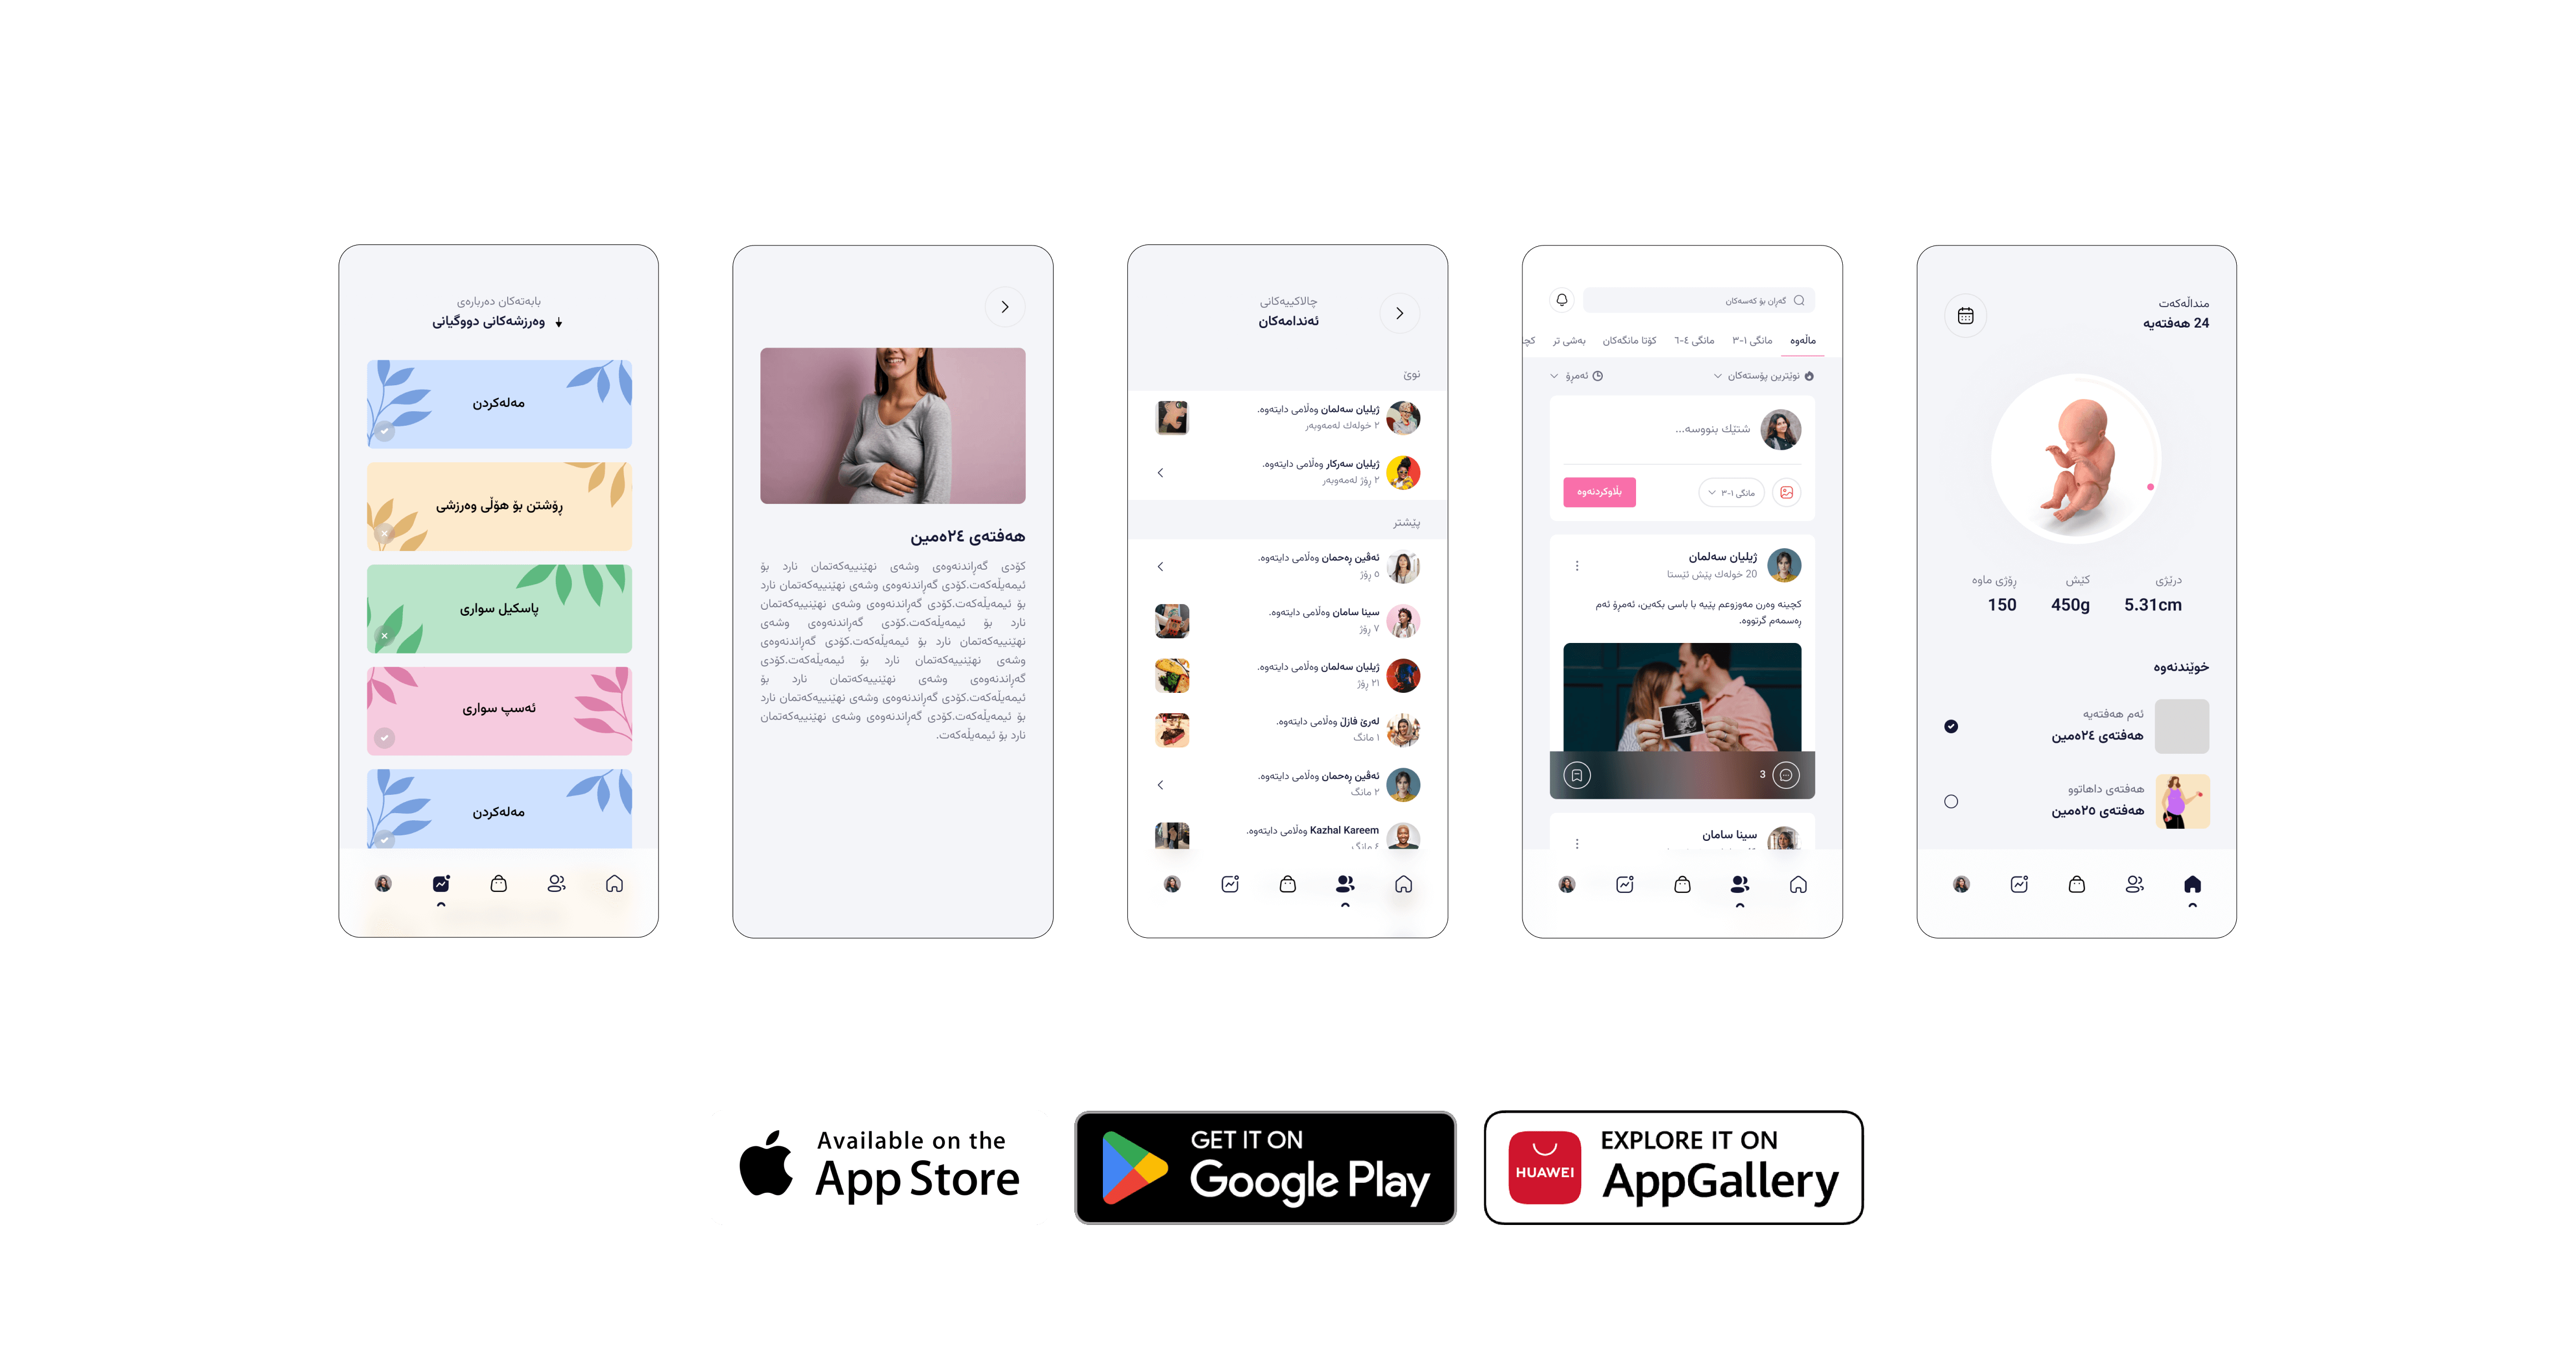

تایبەت بە خانمان

سوڕی مانگانە، قۆناغەکانی منداڵبوون، ئەزموون، زانیاری

تایبەتمەندیەکان

پڕ زانیاریە

پری ڕێکخراره بهو جۆرهی که گونجاوه بۆ ههلومهرجانهی خانمان پێیدا تێپەڕ ئەبن و دهوڵهمهندکراوه به زانیاری تهندروستی پێویست کە لە لایەن پزیشکانی پسپۆڕەوە دانراوه

هاوکاریکردن

لهکاتی بوونی پرسیار یان کێشه هاوکاری ئهکرێت لایهن خانمانهی به ئهزمونهوه

بەشی دووگیانی

بەشی سوڕی مانگانە

بۆچی پری؟

بوونی بهرنامهی پری له نێو ئامێرهکهت گرنگه بۆ تهندروستی خۆت و کۆرپهکهت یاخود وهرگرتنی ئهزموون و زانیاری له خانمانی ترهوه